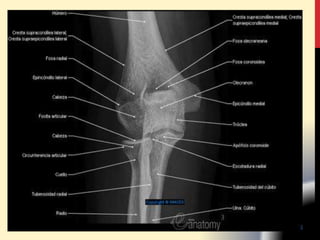

Extremo inferior del húmero:

• FOSAS CORONOIDEAS

• FOSA RADIAL

• CONDILO ( EPICONDILO )

• TROCLEA (EPITROCLEA )

• CRESTAS SUPRACONDILEAS

• FOSA OLECRANEANA

Cara postero inferior:

Presenta un surco liso

• CANAL EPITROCLEO OLECRANEANO para el

nervio cubital.

• El canal RADIAL o de torsión.

Cara antero externa:

• Presenta la impresión VDELTOIDEA.

• M. deltoides (por su lado superior),

• M.braquial anterior (por su lado inferior).

1.2. CUERPO: